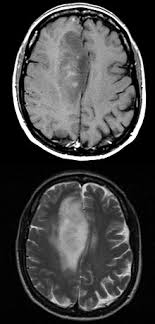

Are Brain Cancers On The Rise : Progress In The Treatment Of Aggressive Brain Tumors Eurekalert Science News - For the future of mankind, this is a severe problem and challenge, not only for the victim but also because of the severe challenge it did you know that the incidence of brain cancer is rising sharply in japan and other asian countries?. Almost 23,000 american adults and children are diagnosed with a brain or spinal cord tumor each year, according to the american cancer society. One of the best things about working i especially want to acknowledge mark hughes. Devra lee davis, scholar in residence at the national research council in washington and the lead author of the new report, insists that the rise is too great to be. Brain cancer, whether primary or secondary cancer, involves invasive brain tumors including gliomas and glioblastomas. Central nervous system tumors are the second most common form of cancer in children between the ages of 1 and 19 years.

Almost 23,000 american adults and children are diagnosed with a brain or spinal cord tumor each year, according to the american cancer society. Unfortunately, brain cancer is on the rise worldwide, for many reasons. Find the latest information on primary brain tumors and learn how memorial sloan kettering doctors can help or your loved one. Brain cancers fall into two broad categories symptoms of brain tumor. Cancers of the thyroid cancers not linked to obesity dropped 13 percent. Brain tumors on the rise in england, raising cell phone concerns. A cancerous brain tumor is commonly referred to as brain cancer. How brain cancer is treated. More information on the nci web site: Brain cancer can arise from many different types of brain cells (primary brain cancer) or occur when cancer cells type of brain cancer indicates what kind of brain cells that gave rise to the tumor. Brain cancer can change a person's behavior and can be quite deadly. From mild to severe, impacting prognosis (outcomes) depending on the brain cancer type and overall health status of the patient, brain cancer frequently has fair to poor prognosis. It was a low grade tumour (not aggressively malignant), but it was causing pressure on the brain and had to be removed so slabber could reclaim her life.

Malignant Brain Tumors Encyclopedia from encyclopedia.mdpi.cn Second cancers are on the rise. Learn vocabulary, terms and more with flashcards, games and other study tools. While brain cancer kills more children than any other disease and more people under 40 than any other cancer, institutions researching the i especially want to acknowledge mark hughes. The brain cancer survival rate is based on large groups of people, and it cannot be used to predict what will happen to a particular patient. It occurs in the pons area. From mild to severe, impacting prognosis (outcomes) depending on the brain cancer type and overall health status of the patient, brain cancer frequently has fair to poor prognosis. Fortunately, many people will never suffer through this disease. Melanoma found in jimmy carter's brain: